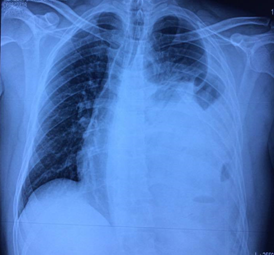

Radiografía anteroposterior de tórax: Se observó una imagen compatible con hernia diafragmática en el hemitórax izquierdo (Fig. 1).

El resultado anterior se ratificó mediante la tomografía axial computarizada simple (Fig. 2) y contrastada de tórax (Fig. 3).

En este paciente los resultados de los estudios imagenológicos fueron determinantes para establecer el diagnóstico definitivo y la causa. Resulta válido destacar que este tipo de hernia se diagnostica inicialmente por el método clínico; sin embargo, el examen de elección es la radiografía de tórax, luego se ratifica mediante la tomografía axial computarizada simple y, por último, a través de la tomografía contrastada.1,4